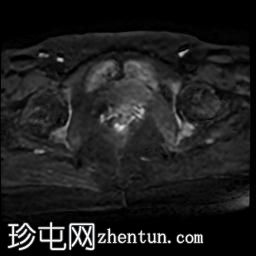

轴位T2加权像

脂肪抑制像

右侧输卵管呈管状囊性扩张,直径达30 mm,提示输卵管积水,呈均匀液体信号,无实性成分。

左侧输卵管亦有轻度扩张,直径26 mm,符合输卵管积水表现。

右侧卵巢可见一单纯性卵巢囊肿,大小约35 x 40 mm,呈正常液体等效信号。

MRI 检查结果显示双侧输卵管积水和右侧卵巢单纯性囊肿。总体而言,所有附件和盆腔检查结果均显示良性 MRI 特征(O-RADS 2 类),无恶性肿瘤迹象。